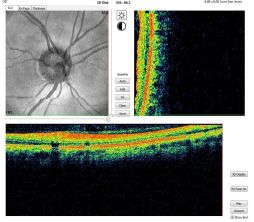

At its inception, OCT images were acquired in a time-domain fashion. Time-domain systems acquire approximately 400 A-scans per second using 6 radial slices oriented 30 degrees apart. Because the slices are 30 degrees apart, care must be taken to avoid missing pathology between the slices.

Spectral-domain technology,[2] on the other hand, scans approximately 20,000-40,000 A-scans per second. This increased scan rate and number diminishes the likelihood of motion artifacts, enhances the resolution, and decreases the chance of missing lesions. Spectral-domain systems increase the signal-noise ratio by image averaging multiple B-scans at the same location. Whereas most time-domain OCTs are accurate to 10-15 microns, newer spectral-domain machines may approach 3-micron resolution. Whereas most time-domain OCTs image 6 radial slices, spectral domain systems continuously image a 6 mm area. This diminishes the chance of inadvertently missing pathology. Spectral-domain systems typically operate at 800 nm-870 nm wavelengths, although longer wavelengths of 1050-1060 nm are being developed for deeper penetration in the tissue.